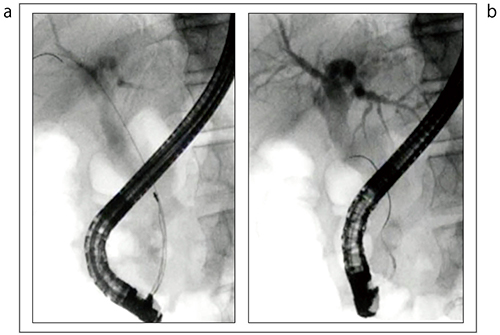

図12は、ガイドワイヤが結石の脇を通り抜けてしまった症例である。本症例では、いったんガイドワイヤを外し、ルートを変更して再度挿入したことで、除去に成功した。積み上げ結石に対しては、下から取っていくことが基本である。

図12 ガイドワイヤルート変更+バスケット操作による結石除去

a:バスケットが結石の横をすり抜けている

b:ルート変更して、再度ガイドワイヤが結石の脇を通るように挿入した